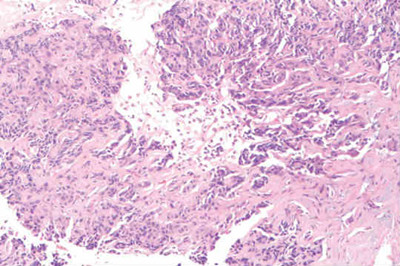

曲美替尼+达拉非尼+化疗治疗BRAF V600E转移性结肠腺癌

引言 曲美替尼(Trametinib、Mekinist)是一种可逆的、高选择性抑制剂,被美国FDA批准用于治疗BRAF V600E/K突变不可切除或转移性黑色素瘤成人患者。达拉非尼(Dabrafenib、Tafinlar)是一种BRAF激酶活性的有效选择性抑制剂。 病例报告 一名33岁的女性有乳糜泻病史,至诊所接受常规随访。结肠镜检查发现可疑肿块。 结肠镜检查显示结肠肝曲周围有3-4cm的恶性病变。活组织检查证实了中分化腺癌。胸腹部和骨盆CT扫描显示,肝脏和肺部不明显,近端横结肠增厚区域附近有小淋巴结,肠系膜上静脉前2cm淋巴结肿大,无其他骨盆肿块或淋巴结肿大。术前CEA水平为1.0 mcg/L。 行腹腔镜右半结肠切除术,并且病理检查确定为具有粘液特征的侵袭性中分化腺癌,肿瘤通过肌层侵入,通过周围脂肪组织进入浆膜表面。边缘为阴性,淋巴血管浸润为阳性,阑尾为良性,31处淋巴结中有5处为转移性腺癌阳性,病理分期为T4aN2a。术后扫描显示,没有转移的迹象。患者接受了12个周期的FOLFOX辅助化疗。 由于出现外周神经病变不良事件,在10个周期后暂停奥沙利铂治疗。术后7个月随访CT扫描显示,肝脏前叶有一处新的异质性肿块,长度为3.3cm,肝脏右后叶另有一处小的衰减灶。PET/CT显示,肝脏病变为FDG高代谢,SUV值为12.6,肝脏活组织检查证实转移性腺癌,与已知的结肠原发肿瘤一致。 切除肝脏病变,边缘阴性。6个月后扫描显示新出现淋巴结肿大,新出现转移性肝脏病变。此时,确认了KRAS突变状态。患者开始使用FOLFIRI+西妥昔单抗进行系统治疗,由于患者接受西妥昔单抗治疗时出现明显皮疹,转为FOLFIRI+贝伐单抗方案。在随访中,患者出现重度的胸腹痛,并被送往医院接受了进一步的症状检查。 在住院期间,患者接受了检查,扫描结果显示,前纵隔存在新的淋巴结病变,肝脏双叶多处新发病变,与疾病进展一致。肝脏活组织检查再次确认转移性结直肠癌(CRC),对组织样本进行全面基因组分析(CGP)。患者继续使用FOLFIRI治疗方案,方案中没有加入贝伐单抗,等待基因组分析结果。 方法 进行经皮肝脏活组织检查,并使用FoundationOne测定法(Foundation Medicine,Inc.,Cambridge,MA,USA)进行组织病理学以及基因组分析。 结果 基因组分析证实,复发肝转移包括7个基因组改变:BRAF V600E以及MYC扩增,CDKN2A(p16INK4a)A57V,TP53 R175H,SMAD4 R361C和两处APC移码插入/缺失(S1545fs*1,T1556fs*3)。没有表明高频突变提示错配修复缺陷的证据。因为存在BRAF V600E和TP53 R175H突变,患者开始接受达拉非尼 (75 mg,每日两次),曲美替尼 (1 mg每日一次),奥沙利铂(85 mg/m2每两周一次)治疗。 在开始治疗后不久,患者出现发烧和寒战及皮疹,但将达拉非尼剂量减少至75 mg每日一次后,症状迅速改善。治疗开始后1个月的CT扫描显示出显著的放射学反应,纵隔淋巴结肿大改善,没有观察到新的肝脏或纵隔病变;3个月时扫描显示部分反应,纵隔淋巴结肿大和局灶性肝脏病变继续消退。 8个月扫描显示,疾病接近完全消退,纵隔淋巴结病变持续消退,肝脏病变完全消退。自上次临床检查以来,患者继续以不间断的方式接受治疗,出现以下副作用:间歇性轻度发烧,腹痛,持续但易于控制的皮疹。 本内容为医伴旅版权所有,转载请注明出处。 医伴旅:寻找优质医疗资源,伴您走上康复之旅